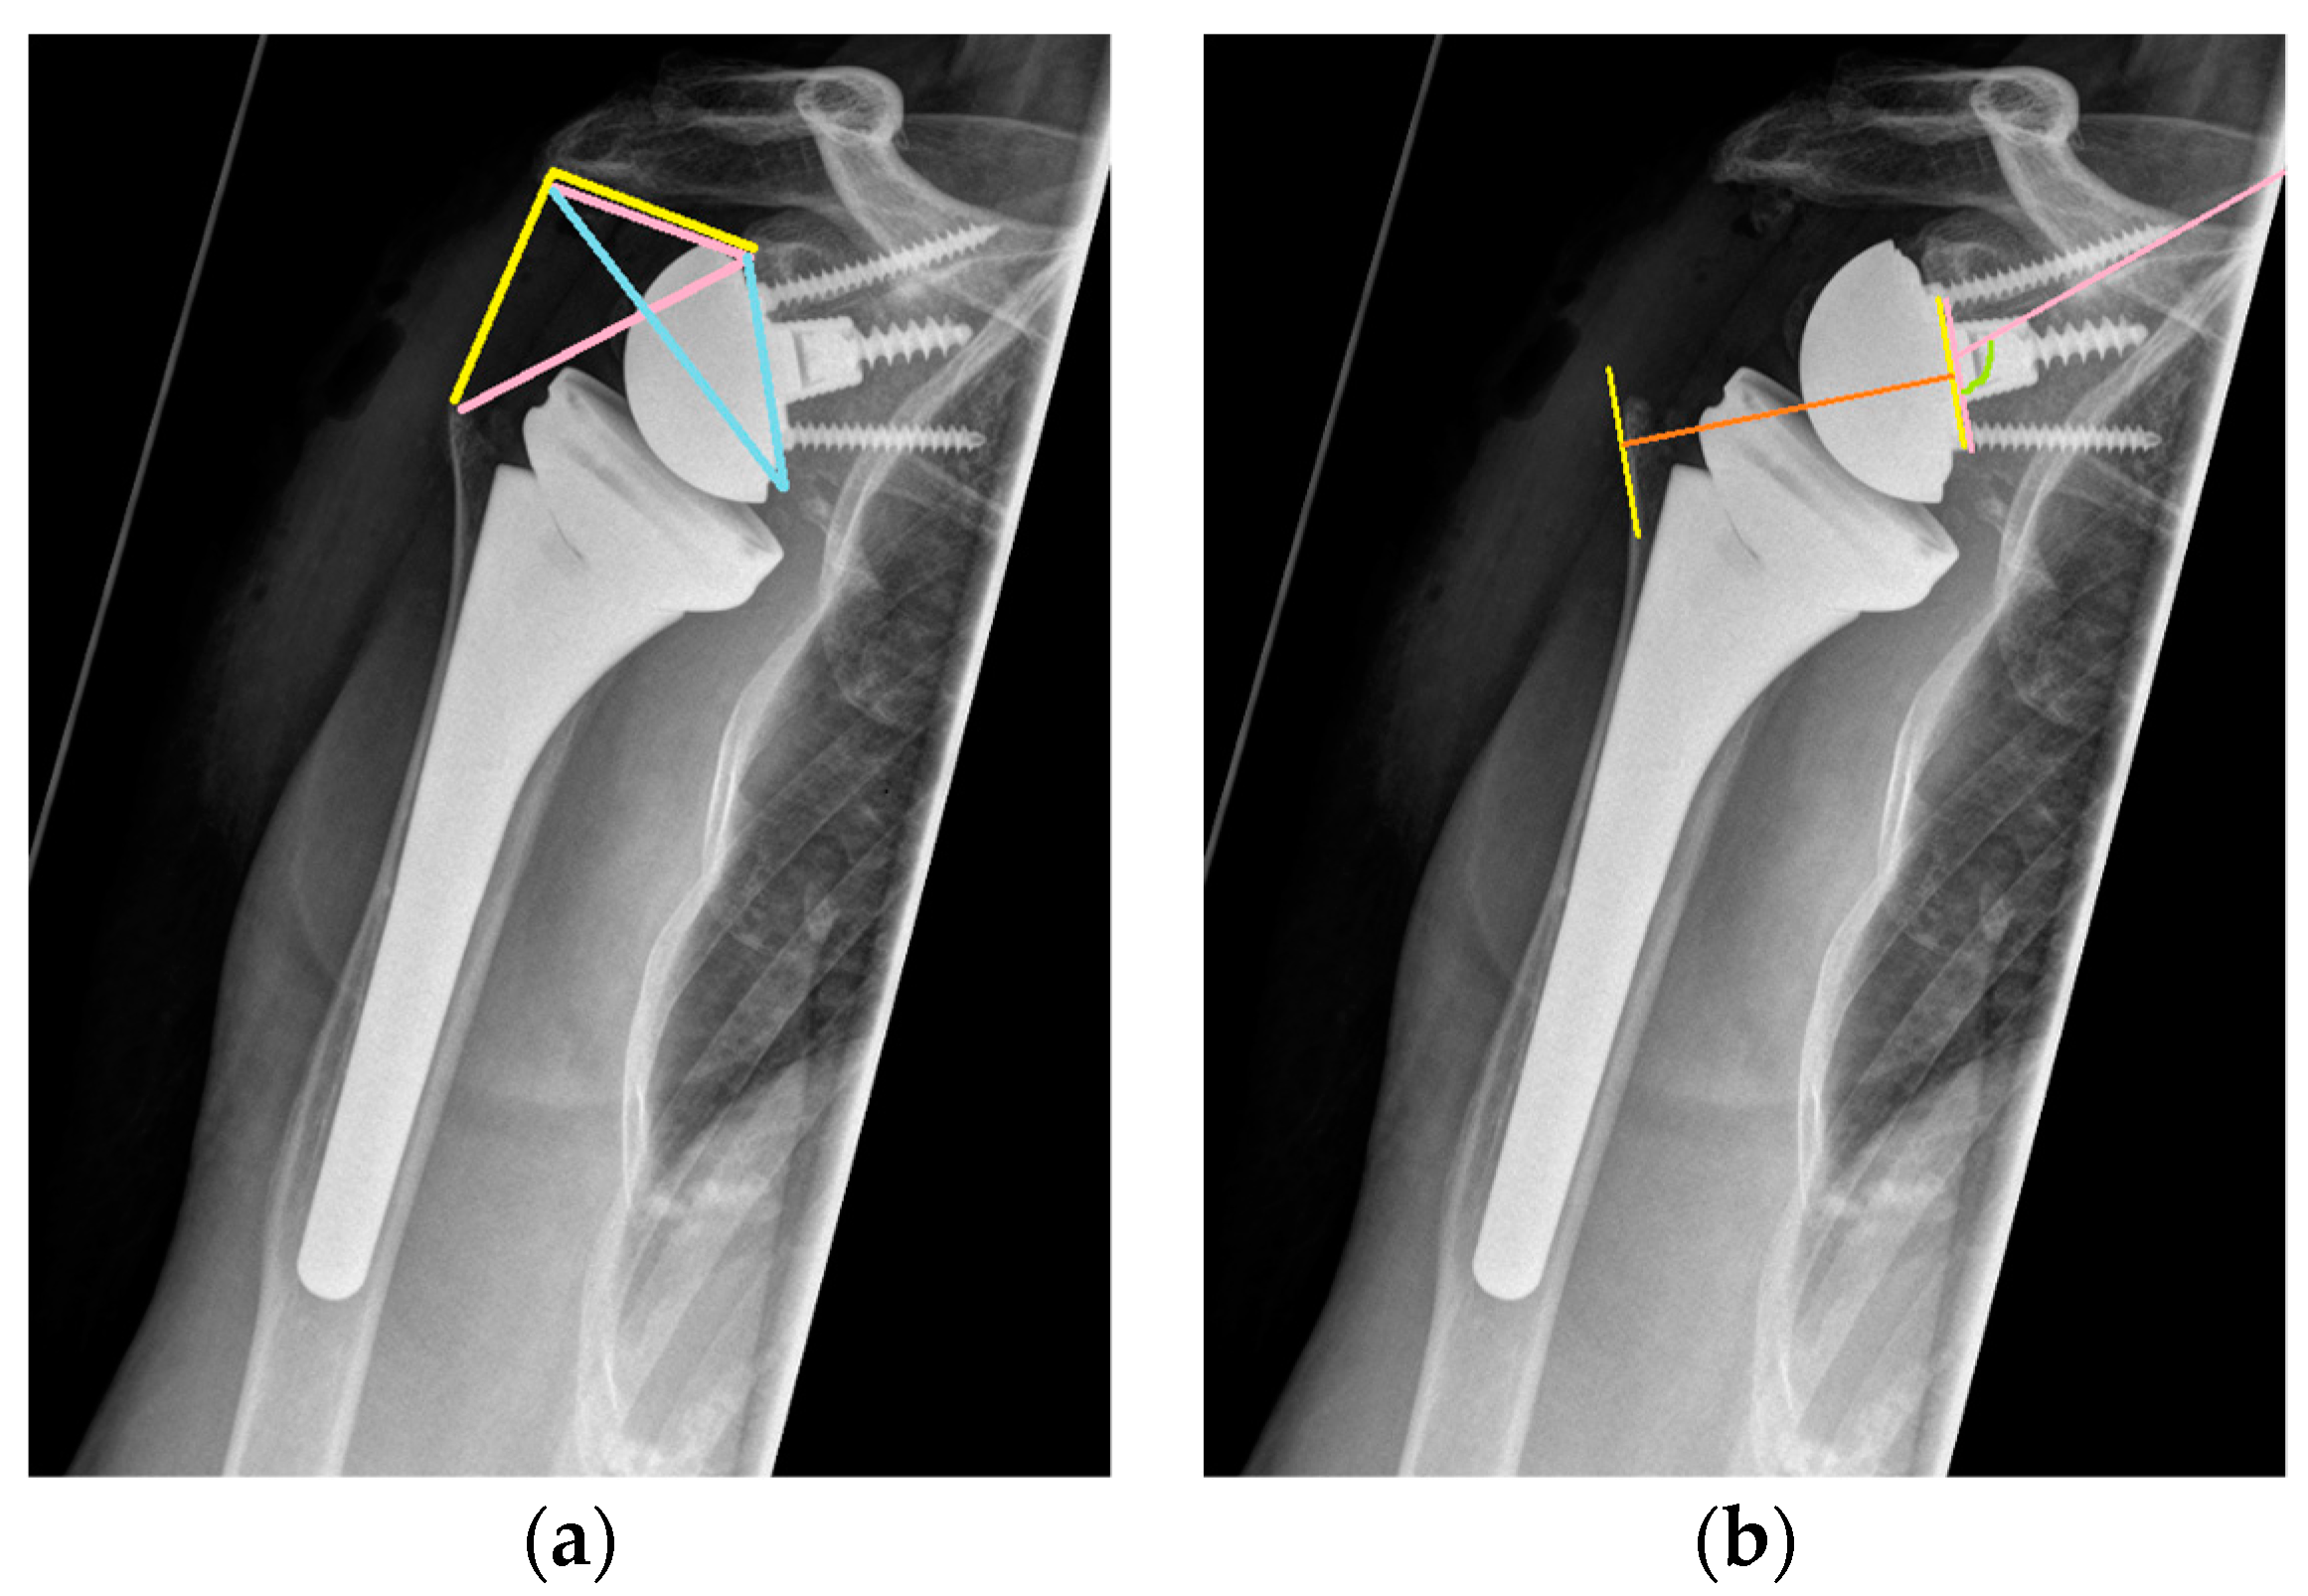

2.4. Radiographic Assessment